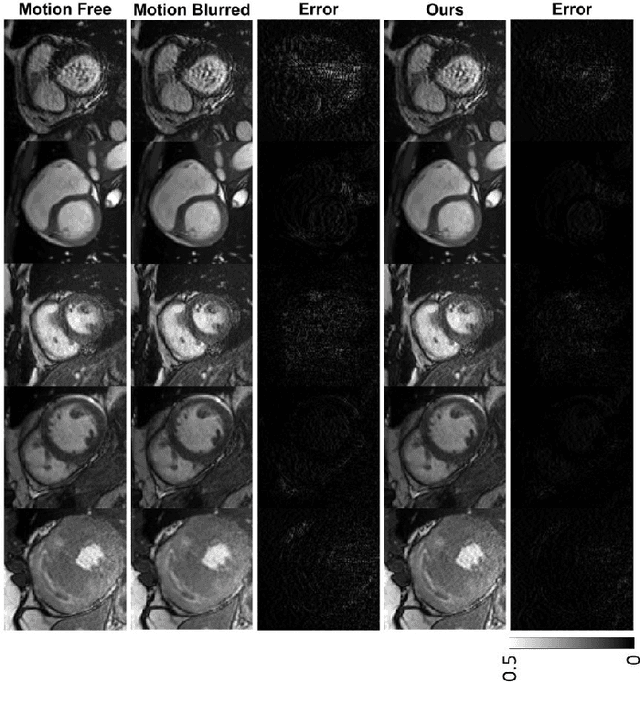

Abstract:Cine cardiac magnetic resonance imaging (MRI) is widely used for diagnosis of cardiac diseases thanks to its ability to present cardiovascular features in excellent contrast. As compared to computed tomography (CT), MRI, however, requires a long scan time, which inevitably induces motion artifacts and causes patients' discomfort. Thus, there has been a strong clinical motivation to develop techniques to reduce both the scan time and motion artifacts. Given its successful applications in other medical imaging tasks such as MRI super-resolution and CT metal artifact reduction, deep learning is a promising approach for cardiac MRI motion artifact reduction. In this paper, we propose a recurrent neural network to simultaneously extract both spatial and temporal features from under-sampled, motion-blurred cine cardiac images for improved image quality. The experimental results demonstrate substantially improved image quality on two clinical test datasets. Also, our method enables data-driven frame interpolation at an enhanced temporal resolution. Compared with existing methods, our deep learning approach gives a superior performance in terms of structural similarity (SSIM) and peak signal-to-noise ratio (PSNR).